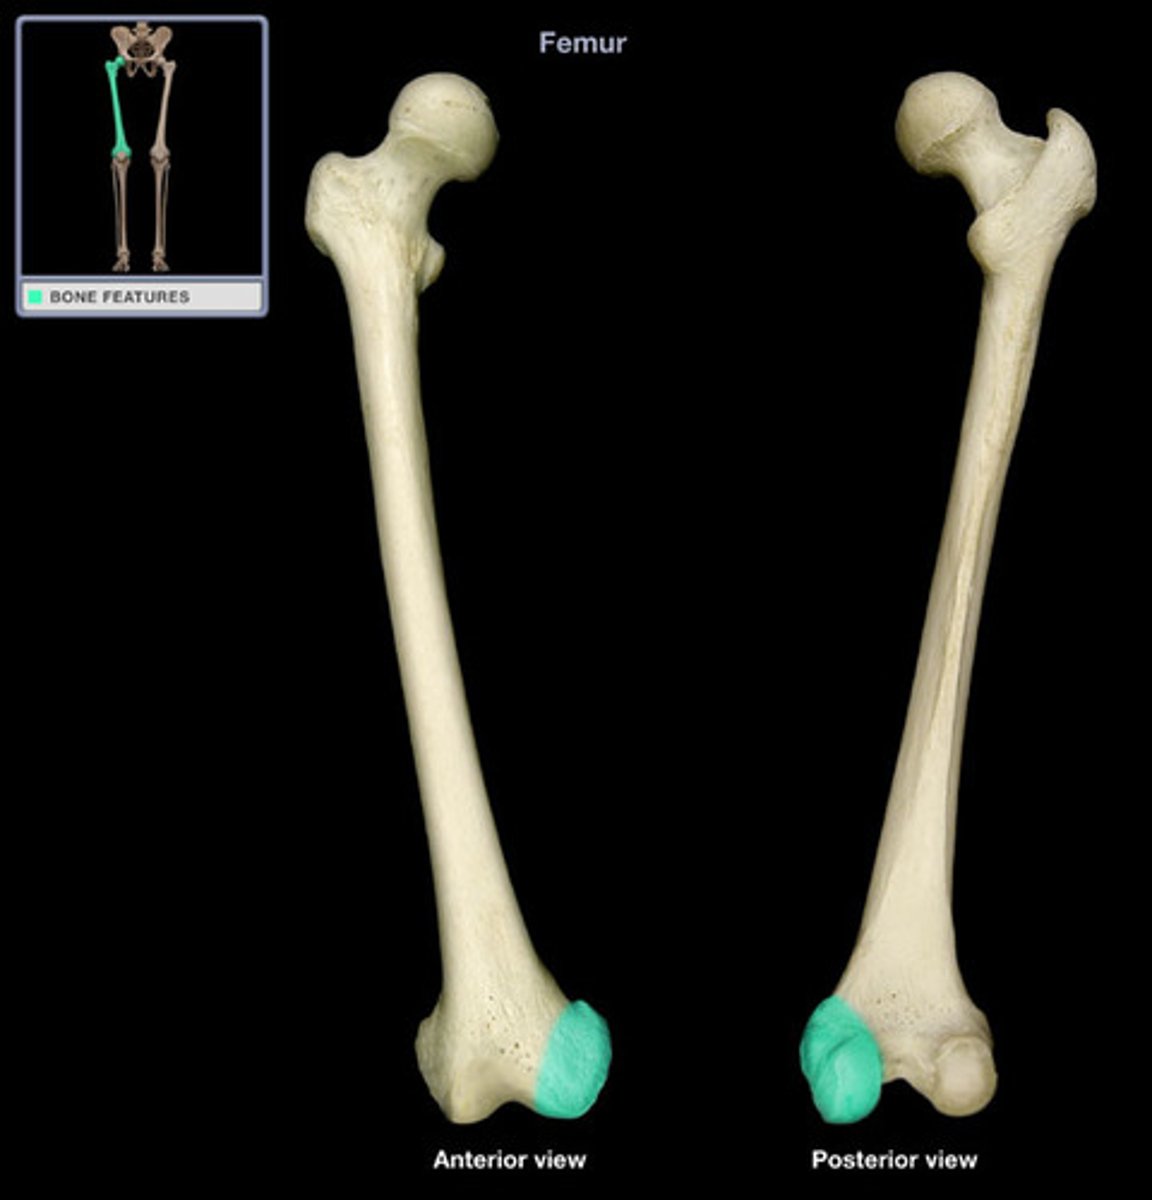

Femur

Medial Condyles of the Femur

Lateral Condyles of the Femur

Medial Epicondyles of the Femur

Lateral Epicondyles of the Femur